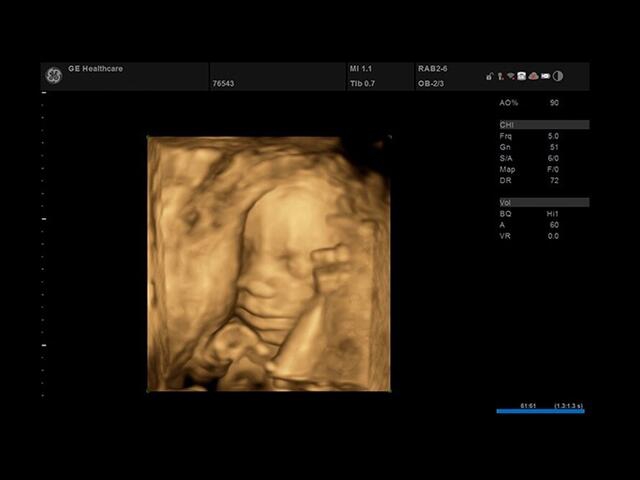

• SonoBiometry : Эта функция позволяет быстро измерить биометрические параметры плода, такие как длина бедра, окружность головы, окружность живота и длина кости. Это важно для контроля развития плода и оценки его состояния.

• VOCAL : Это 3D-инструмент, который позволяет рассчитывать объем участков эксцентрической формы или сложных анатомических структур. Он полезен при анализе и измерении объемных образований внутри органов.

• Автоматичексая биометрия плода (БПР, ОГ, ОЖ, ДБ) - Да